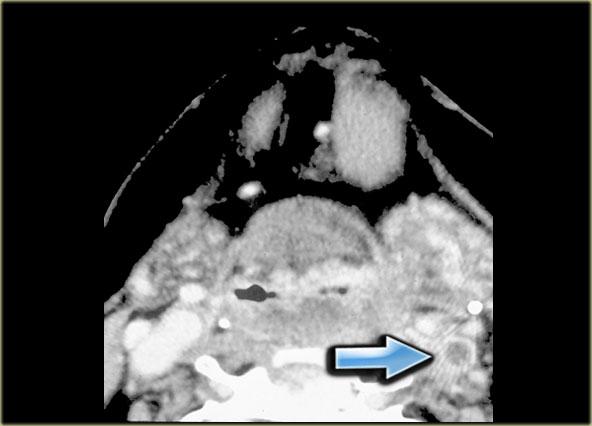

Bên trái là hình CT ở mức sụn giáp.

Có một khối không đều nằm trung tâm ở xoang lê bên phải.

Khối này nằm trong khoang tạng.

Ở vùng này, khối u thường gặp nhất là ung thư biểu mô tế bào vảy.

Chẩn đoán này đã được xác nhận qua sinh thiết.

Lưu ý khoang sau hầu (mũi tên vàng).

Đây là khoang ảo chỉ chứa một ít mô mỡ.